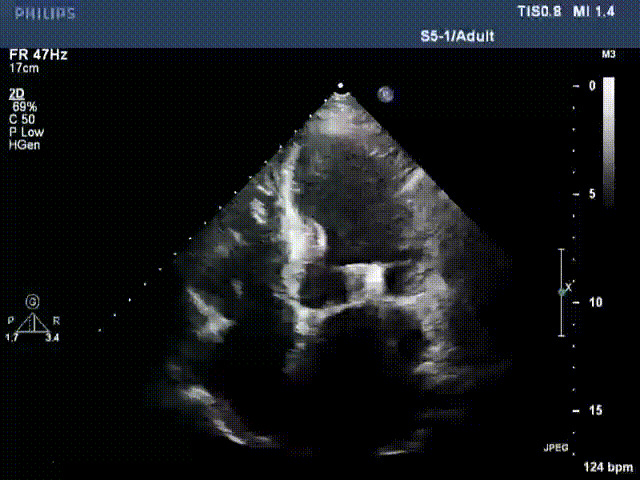

術后超聲顯示二尖瓣反流消失,瓣膜夾穩定

出院前隨訪超聲

接受治療的是一例器質性重度二尖瓣反流(DMR)患者,主訴“反復活動后胸悶,氣促3年余”。術前超聲顯示,雙房增大,二尖瓣脫垂伴重度反流,輕度三尖瓣反流,輕度肺高壓,升主動脈增寬。手術經股靜脈-房間隔入路,采用全身麻醉插管,在TEE和DSA引導下完成房間隔穿刺。置入JensClip瓣膜夾系統后,在左房調整瓣膜夾的位置和軸向,后進入左室,在TEE引導下捕捉二尖瓣前后瓣葉,并關閉瓣膜夾。經TEE反復確認手術效果后最終鎖定并釋放瓣膜夾。術后即刻超聲顯示瓣膜夾位置穩定,功能良好,術前二尖瓣反流4+,術后0反流,肺靜脈逆流和左房壓都顯著好轉,手術圓滿成功(以上數據都來源于醫院的臨床記錄)。術后患者狀態良好,目前已安排出院。